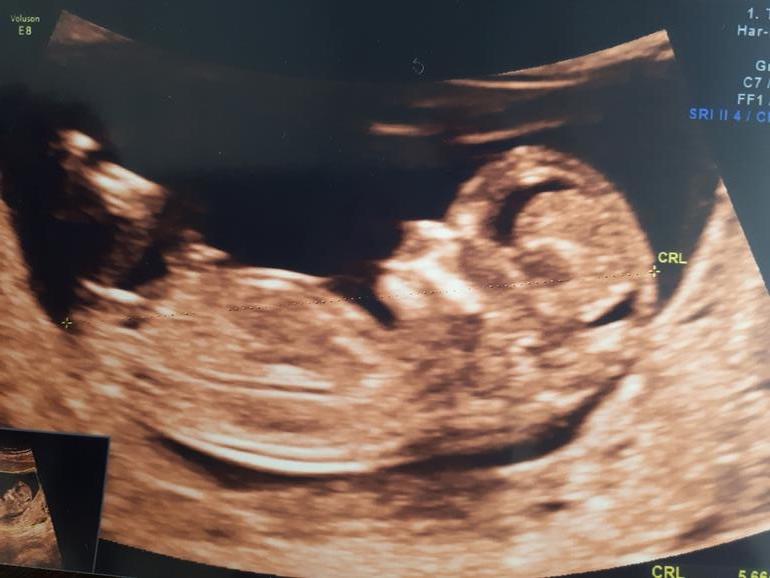

Наши 12 недель

Виктория, а вам пол предположили по бугорку или как? мне врач сказала,,но все пишут не верить полу по узи в 12 недель

Да, по бугорку, по его наклону. У сына был к верху, а тут смотрел вниз. Да, я и по своим преметам предполагаю девочку.

мне врач тоже по бугорку....ну не знаю, все фотку гляжу пытаюсь понять

Фотку можно глянуть?

да, конечно, посмотрите опытным глазом

Девочку пророчат?

вы думаете девочка? врач сказала, что девочка

Да, я думаю девочка